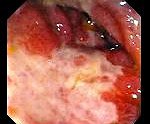

При колоноскопии на ранних стадиях ишемического колита слизистая оболочка отечна, легко кровоточит, со сливными геморрагиями. Могут быть видны синюшные буллезные выпячивания, создающие рентгенологическую картину наподобие «отпечатка большого пальца». В более выраженной стадии обнаруживают неправильной формы язвы, окруженные геморрагически измененной слизистой оболочкой. В последующем возможна трансформация язв в псевдополипы.